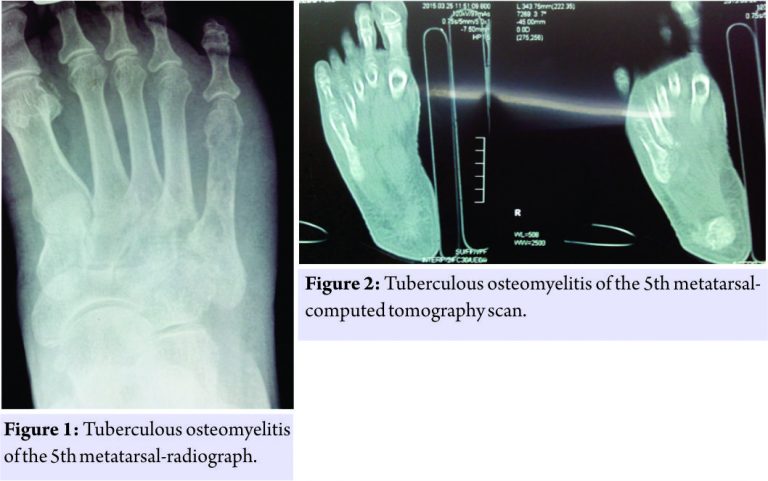

Case 1

A 65-year-old woman from a low socioeconomic background presented with pain and swelling of the right foot for 2 months. There was no history of trauma, fever, chronic cough, or weight loss. There was no history of pulmonary tuberculous (TB) or any Koch’s contact. The patient was taking analgesics on and off as prescribed by a general practitioner. On physical examination, there was a diffuse swelling over the lateral aspect of the dorsum of the midfoot and was associated with tenderness. There was no regional lymphadenopathy. The laboratory values showed haemoglobin of 11 g % and raised erythrocyte sedimentation rate (ESR) of 32 mm/hr. Total leukocyte count was 11,950 cells/cu mm with lymphocytosis (differential leukocyte count- P 32, L 62, E 4, M 2). HIV and hepatitis B virus surface antigen were negative. Foot radiograph and computed tomography (CT) scan showed osteolytic lesion in the bodies of fourth and fifth metatarsal (Fig. 1 and 2). Chest radiograph was normal. The patient underwent curettage which revealed cheesy material. K-wiring of the fifth metatarsal was done and the tissue was sent for histopathological examination. Biopsy of the lesion showed granulomatous lesion with Langhans giant cells. Ziehl–Neelsen staining was negative for acid-fast bacilli. At latest follow-up of 12 months, the lesion healed and anti-TB treatment was stopped.